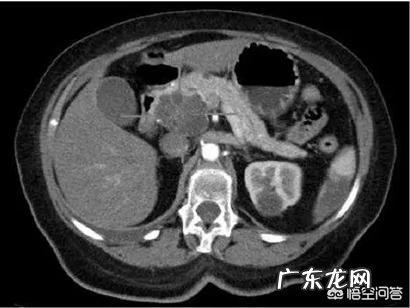

2、B型超声可以作为初筛 。CT检查才是目前检查胰腺最佳的无创性影像检查方法 , 主要用于胰腺癌的诊断和分期 。增强扫描能够较好地显示胰腺肿物的大小、部位、形态、内部结构及与周围结构的关系 。能够准确判断有无肝转移及显示肿大淋巴结 。